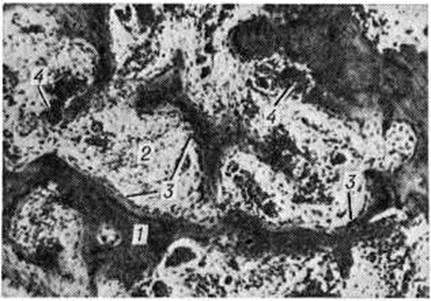

Новообразованная костная ткань лишена функциональный дифференцировки, однотипна при любой локализации процесса. Эта ткань разрастается среди предсуществующих костных структур, постепенно занимая все более значительные пространства кости. Она построена из мелких, примитивных афункциональных костных перекладин, частично сохраняющих остеоидный характер. Рисунок костных пластин неотчётливый. Количество и зрелость костных перекладин могут быть различными. Костные перекладины окружены нежно волокнистой остеогенно-потентной тканью (рисунок 8), содержащей большое количество кровеносных капилляров, вокруг которых располагаются мелкие одноядерные клетки с тёмно-базофильными ядрами и узким розоватым ободком цитоплазмы. Новообразованная костная ткань отличается признаками интенсивного костеобразования и резорбции неполноценного костного вещества — вблизи костных перекладин располагаются цепочки и скопления клеток остеобластического ряда, на поверхности костных перекладин в лакунах залегают многочисленные остеокласты.